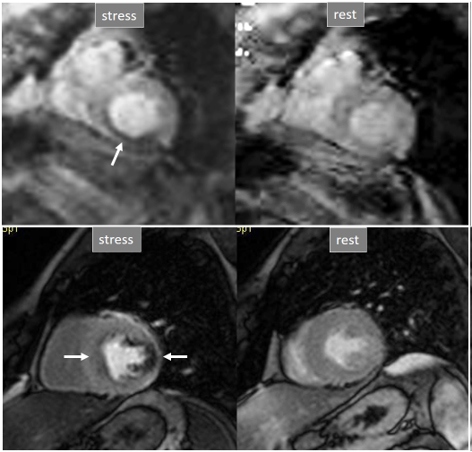

Perfusion defects in different territories can be detected in case of multivessel disease (Fig. 7) and, in patients with severe 3-vessel CAD, the perfusion study may show a global, intense, persistent defect which is readily recognizable (Fig. 8).

Fig. 7.Two-vessel perfusion defect. Stress perfusion defects at the anterior (white arrows) and inferior (black arrows) walls, not present at rest. Angiography (right panels) shows significant stenoses (white arrows) of the LAD (upper panel) and the right coronary artery (RCA) (lower panel).